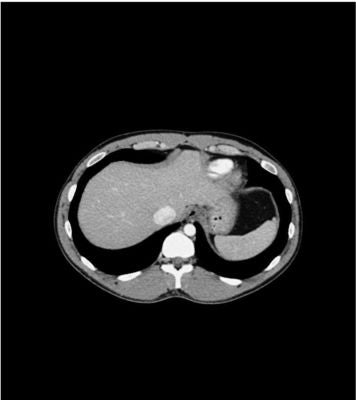

Description

This phantom simulates a contrast medium-enhanced abdomen in the portal venous phase. It covers the eleventh thoracic vertebra to the fourth lumbar vertebra (partially included). The phantom can be used in CT (including CBCT) to evaluate and optimize imaging performance and post-processing applications, including AI-enabled applications. It is also suited for training purposes. The phantom provides a detailed and realistic simulation of soft and bone tissue. Air voids are filled with a cellulose-polymer composite of approx. -160 HU.